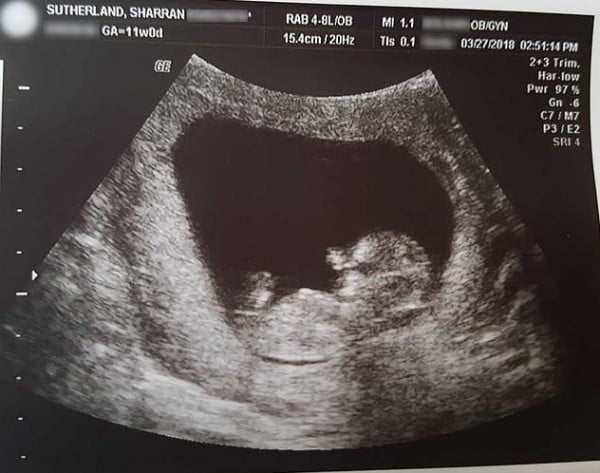

ووفق ما ذكرت صحيفة "ذا صن" البريطانية، فإن شاران ساثرلاند (40 عاما) التقطت عددا من الصور الصادمة للجنين (3 أشهر ونصف) بعد إجهاضه، وهو في طور النمو.

وبلغ طول الجنين 10 سنتمترات ووزنه 26 غراما فقط، ويمكن، من خلال الصور، رؤية وجهه الكامل ويديه وقدميه. وتم حفظ الجنين لمدة أسبوع في الثلاجة، قبل دفنه تحت شجيرة تتواجد في البيت.

وحث الأطباء شاران على إجهاض طفلها، بعد أن أظهرت عملية التصوير بالموجات فوق الصوتية أن قلبه توقف عن النبض.